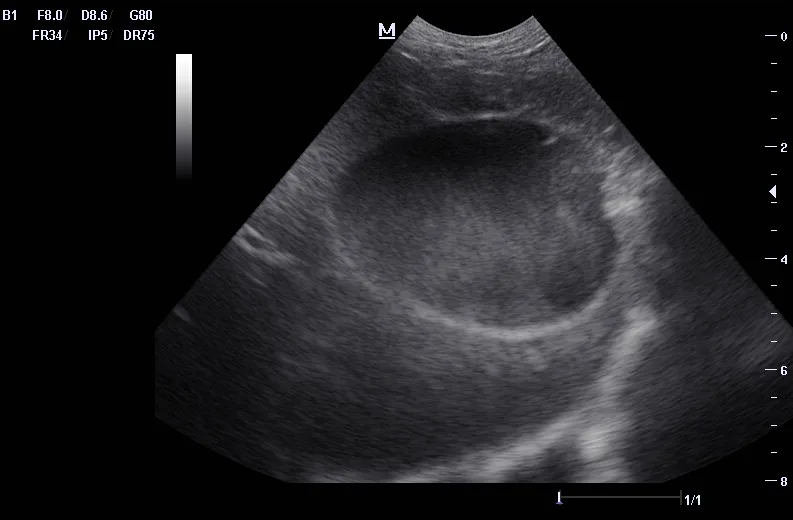

Ultrasound can be useful in evaluating the size, contour, and internal architecture of the prostate. A normal prostate appears homogeneous (Figure 1). The prostate becomes heteroechoic as a result of inflammation, hyperplasia, and neoplasia (Figure 2). The prostatic parenchyma can be focally or diffusely hypoechoic in cases of acute prostatitis or prostatic abscessation (Figure 3), as well as hyperechoic in cases of chronic prostatitis (Figure 4).

Ultrasound image of a prostatic abscess.

FIGURE 3

Prostatic abscess with a focal hypoechoic area